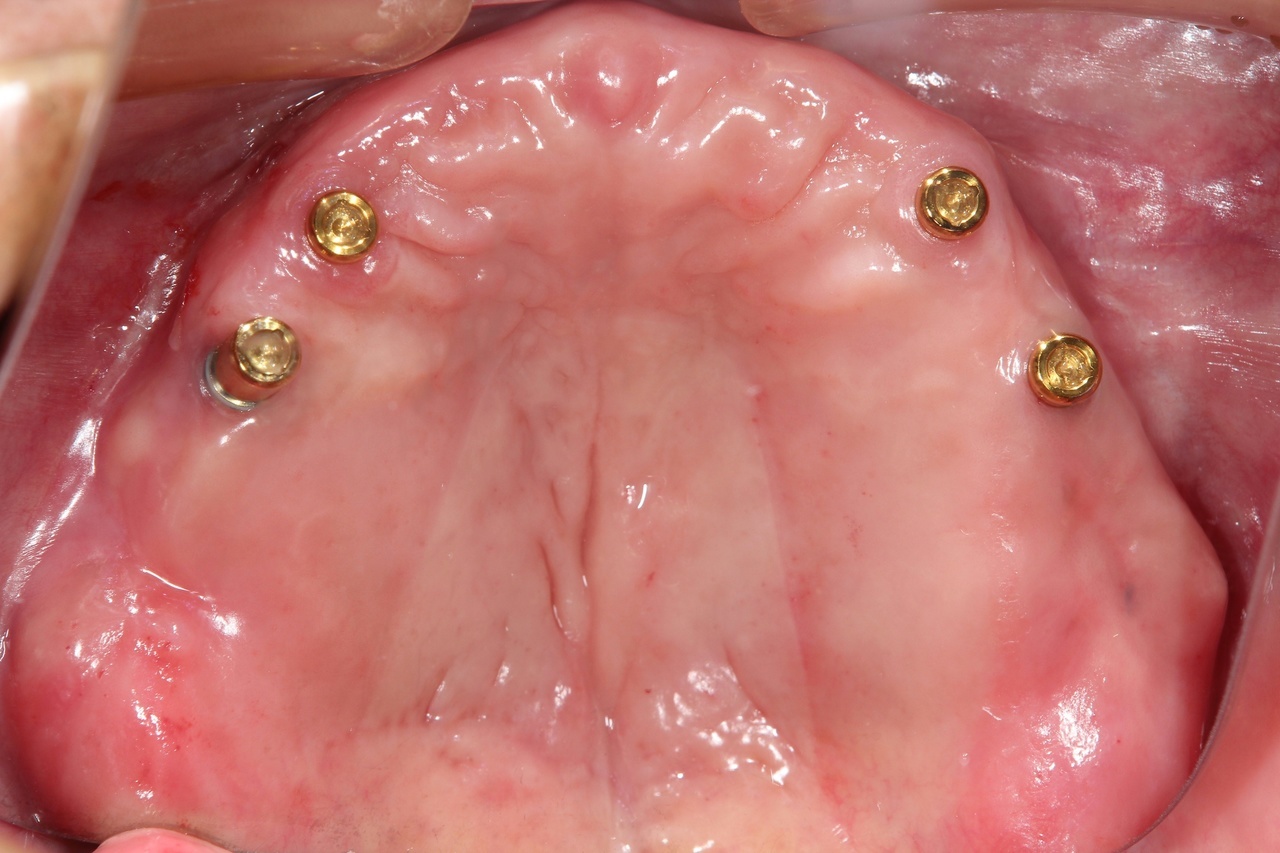

インプラントオーバーデンチャー<ロケータータイプ> (沼津市在住 男性)

インプラントを埋め込み、固定用のロケーターを装着し、入れ歯をしっかりと固定する治療法です。

少ない本数でがっちり噛める治療法です。取り外し可能でしっかり固定できるので、入れ歯の誤飲の心配がなく、手入れがしやすいので寝たきりになっても安心に使用出来ます。

しっかり噛むことで踏ん張りがきくので転んで骨折するリスク回避にもなります。

● オーバーデンチャーを外した状態

● オーバーデンチャーを付けた状態

インプラントオーバーデンチャー

インプラント4本+入れ歯:2,100,000円+税

静脈内鎮静法:0円

上顎と下顎に、インプラント4本+入れ歯、を作る場合 総額:4.200.000+税

骨の条件が良ければ、下顎の場合はインプラントの本数を減らすことができます。

【インプラント2本+入れ歯】1,550,000円+税

【インプラント3本+入れ歯】1,825,000円+税